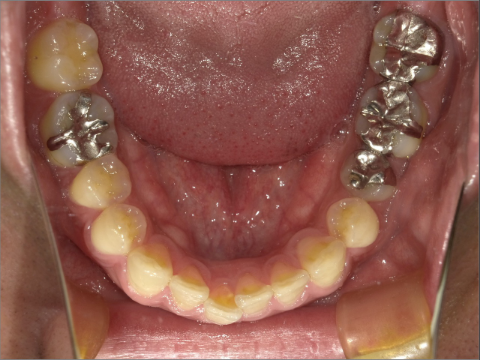

ご年齢 35歳男性

治療期間 2022/08/22〜2023/03/24(1年5ヶ月)

診断 110,000円(税込)

アライナー 550,000円(税込)

リテーナー 55,000円(税込)

BEFORE

AFTER